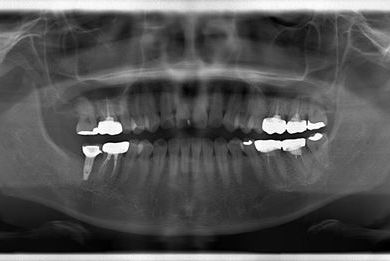

| 性別/年齢 | 女性 / 39歳 | ||||||||||||||||||||||||||||||||

| 主訴 | 右奥歯の虫歯と、右奥のインプラント治療について相談。 | ||||||||||||||||||||||||||||||||

| 治療方針 | 右下奥欠損部分をインプラント治療にて、機能的・審美的回復を行う。 | ||||||||||||||||||||||||||||||||

| 治療内容 | インプラント1本、ハイブリッドセラミッククラウン1本 | ||||||||||||||||||||||||||||||||